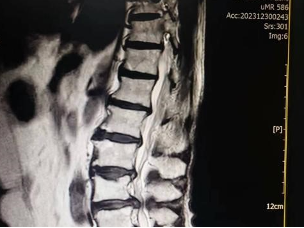

腰椎間盤突出癥MRI